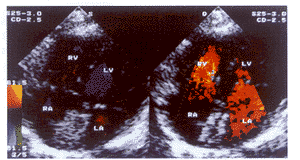

体表超声监测经皮穿刺闭合继发孔房间隔缺损2例

经皮穿刺继发孔房间隔缺损闭合术要求采用食道超声进行监测 ......